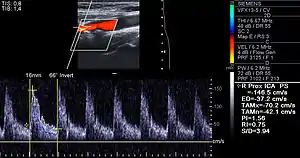

Carotid arteries supply blood to the brain and neck.[24] Marked narrowing of the carotid arteries can present with symptoms such as: a feeling of weakness; being unable to think straight; difficulty speaking; dizziness; difficulty in walking or standing up straight; blurred vision; numbness of the face, arms and legs; severe headache; and loss of consciousness. These symptoms are also related to stroke (death of brain cells). Stroke is caused by marked narrowing or closure of arteries going to the brain; lack of adequate blood supply leads to the death of the cells of the affected tissue.[25]

Besides the traditional diagnostic methods such as angiography and stress-testing, other detection techniques have been developed in the past decades for earlier detection of atherosclerotic disease. Some of the detection approaches include anatomical detection and physiologic measurement.

Examples of anatomical detection methods include coronary calcium scoring by CT, carotid IMT (intimal media thickness) measurement by ultrasound, and intravascular ultrasound (IVUS). Examples of physiologic measurement methods include lipoprotein subclass analysis, HbA1c, hs-CRP, and homocysteine. Both anatomic and physiologic methods allow early detection before symptoms show up, disease staging, and tracking of disease progression. Anatomic methods are more expensive and some of them are invasive in nature, such as IVUS. On the other hand, physiologic methods are often less expensive and safer. But they do not quantify the current state of the disease or directly track progression. In recent years, developments in nuclear imaging techniques such as PET and SPECT have provided ways of estimating the severity of atherosclerotic plaques.[78]